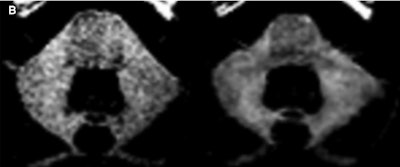

The two patients who received 37 and 44 single-dose macrocyclic GBCA injections, respectively, showed visible dentate nucleus enhancement but no enhancement on baseline MR images.

Two neuroradiologists then analyzed T1-weighted MR images to evaluate any differences between baseline scans and the last exam in terms of visual dentate nucleus signal enhancement.

More specifically, the duo rated signal intensity separately for the left and right dentate nucleus, with 0 as no enhancement, 1 as slight enhancement, and 2 as strong enhancement. The neuroradiologists also rated whether enhancement was confined to the dentate nucleus (1) or it went beyond the dentate nucleus (2).